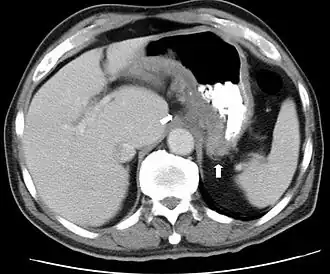

Bei den bildgebenden Verfahren der Radiologie – insbesondere den anhand der Untersuchungsdaten errechneten Darstellungen von Körperquerschnitten bestimmter Schichtdicke (Tomographie) – spielen Transversalschnitte eine wichtige Rolle. Sie stellen die aufgenommenen Bilddaten in verschiedenen Transversalebenen dar, die mit bestimmten Abständen längs der Körperachse aufeinander folgen und so in axialer Schichtung ein Bild des Körpers geben. Bei der tomographischen Untersuchung wird eine Serie transaxialer Schnittbilder erstellt, die den untersuchten Körper Schicht für Schicht transversal darstellen.[1]